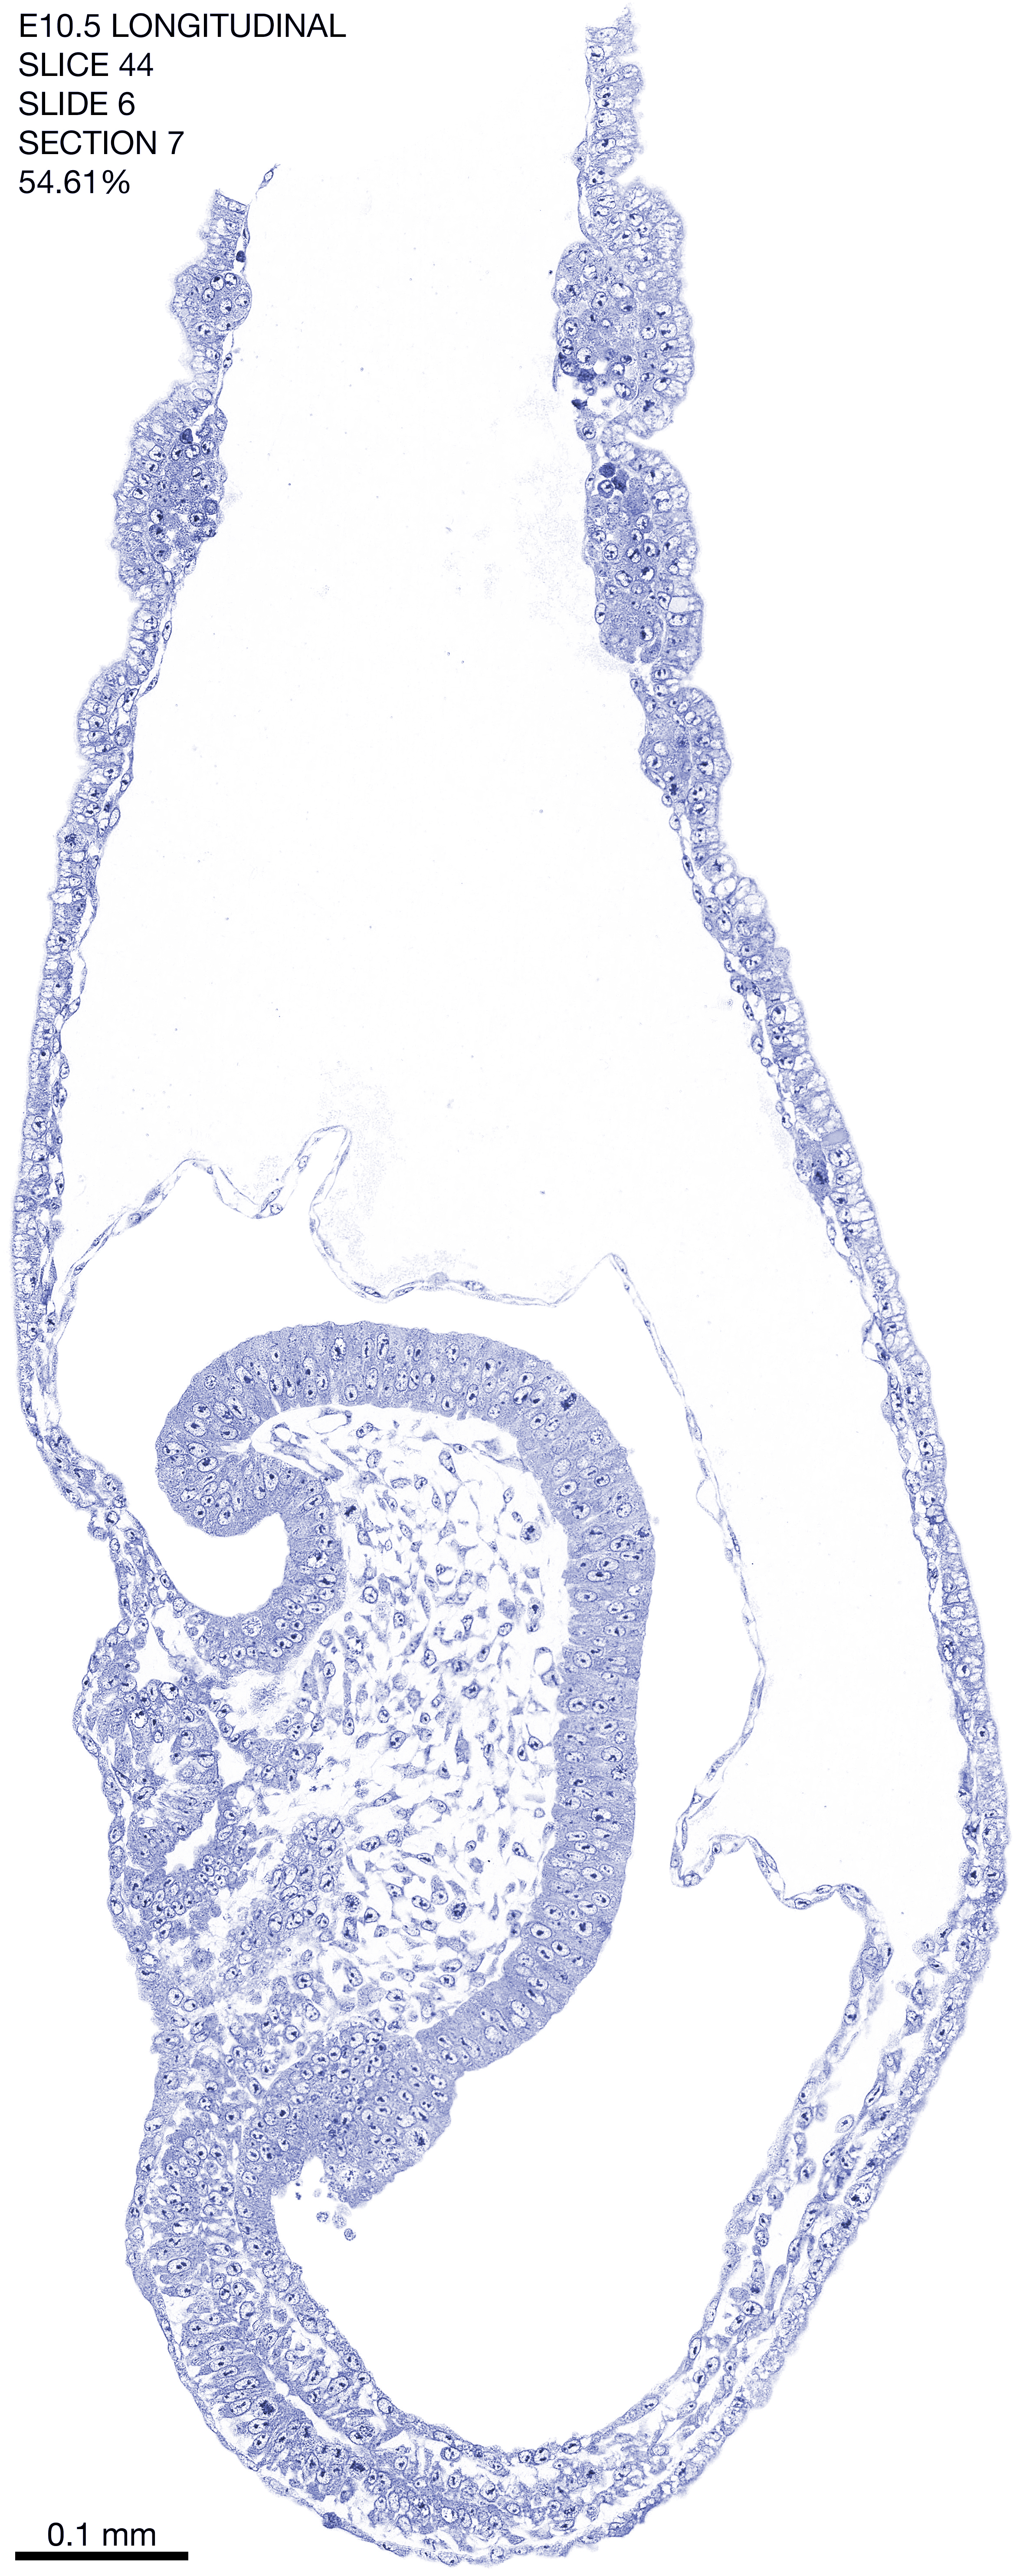

E10.5 Longitudianal Archive This page contains jpg files of ALL SLICES (each 3µm thick) that were scanned of the E10.5 longitudinally cut specimen. Download: Large | High Res Download: Large | High Res Download: Large | High Res Download: Large | High Res Download: Large | High Res Download: Large | High Res Download: Large | High Res Download: Large | High Res Download: Large | High Res Download: Large | High Res Download: Large | High Res Download: Large | High Res Download: Large | High Res Download: Large | High Res Download: Large | High Res Download: Large | High Res Download: Large | High Res Download: Large | High Res Download: Large | High Res Download: Large | High Res Download: Large | High Res Download: Large | High Res Download: Large | High Res Download: Large | High Res Download: Large | High Res Download: Large | High Res Download: Large | High Res Download: Large | High Res Download: Large | High Res Download: Large | High Res Download: Large | High Res Download: Large | High Res Download: Large | High Res Download: Large | High Res Download: Large | High Res Download: Large | High Res Download: Large | High Res Download: Large | High Res Download: Large | High Res Download: Large | High Res Download: Large | High Res Download: Large | High Res Download: Large | High Res Download: Large | High Res Download: Large | High Res Download: Large | High Res Download: Large | High Res Download: Large | High Res Download: Large | High Res Download: Large | High Res Download: Large | High Res Download: Large | High Res Download: Large | High Res Download: Large | High Res Download: Large | High Res Download: Large | High Res Download: Large | High Res Download: Large | High Res